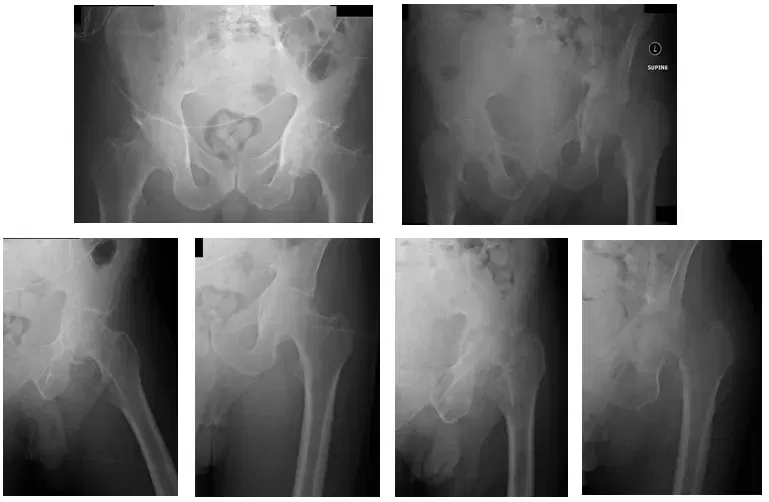

Patient is a 55 year old male who came in complaining of bilateral hip pain that he stated had been increasing over the past several months. Patient came in with x-rays to review, which indicated that he had bilateral arthritis of the hip joints. X-rays are shown below.

X-Rays show bilateral hip arthritis with worse findings of arthritis in the left hip joint

X-Rays also show severe erosive change of the left hip and a basicervical fracture at the femoral neck. Also shown is mild axial migration of the femoral head of the right hip.